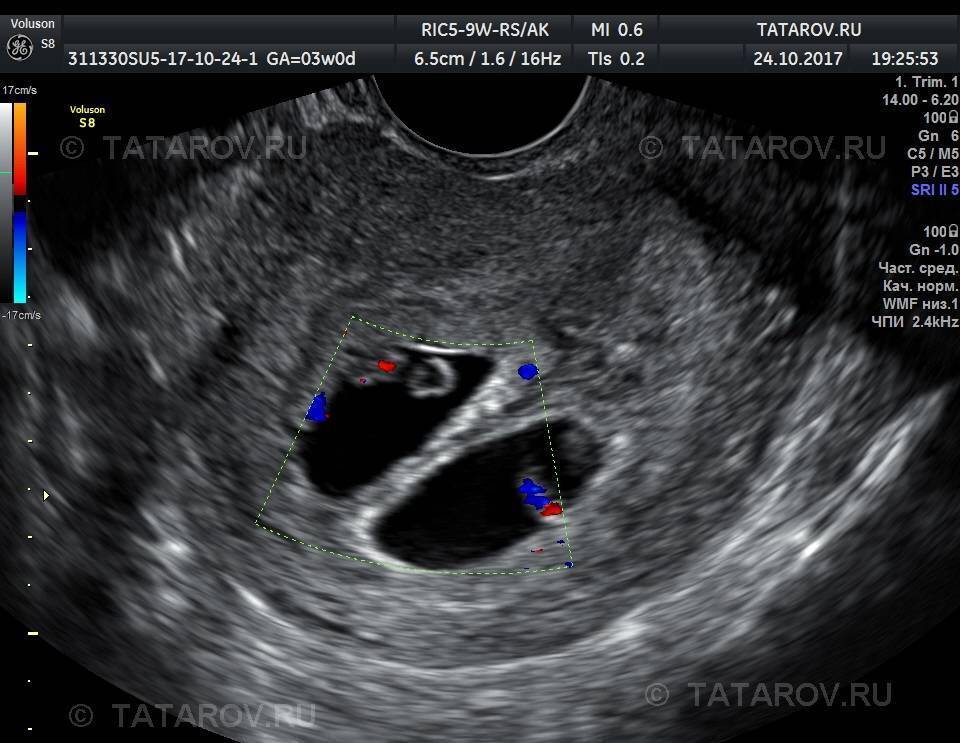

Увидеть двойняшек на мониторе при ультразвуке можно начиная с самых ранних сроков. В это время малыши только-только начинают оформляться, и на экране видно просто 2 темных пятнышка. Но у каждого из них уже есть маленькое сердечко, которое вполне реально услышать.

Если будущая мама впервые узнала о двойняшках на первом плановом ультразвуке в 9-11 недель, она может увидеть полноценных эмбрионов длиной в 4,5-4,8 см. Малыши в это время уже двигаются, у них сформированы внутренние органы, появились пальчики. К 14-й неделе плоды уже достигают в длину 12 см – в это время мамин животик начинает активно расти. В 12 недель длина каждого из близнецов – около 6 см, вес – приблизительно 8 гр.

При проведении ультразвукового исследования на качественном современном оборудовании высококвалифицированным специалистом многоплодная беременность может быть диагностирована уже на 5-й неделе. На мониторе будет видно 2 и более эхонегативных образования, если развиваются разнояйцевые близнецы.

При беременности однояйцевыми близнецами диагностика затруднена. Выявить такую беременность можно примерно на 7–8 неделе, когда зародыши хорошо визуализируются. Однако и в этом случае возможна ошибка.

УЗИ на ранних сроках проводят трансвагинальным способом. Женщина ложится на кушетку на спину, сгибает в коленях и разводит в стороны ноги, диагност надевает на вагинальный датчик презерватив и вводит его глубоко во влагалище.

В ходе исследования сонолог определяет размеры матки, плодного яйца и эмбриона, количество эмбрионов (или плодов, если исследование проводится после 8-й недели беременности), их расположение в матке и место локализации хориона или плаценты (после 12-й недели). Также оценивается развитие малышей, наличие или отсутствие у них патологий или маркеров хромосомных аномалий.